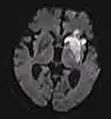

| Apparent diffusion coefficient | ADC | Reduced T2 weighting by taking multiple conventional DWI images with different DWI weighting, and the change corresponds to diffusion.[76] | Low signal minutes after cerebral infarction (pictured).[77] | ![]() | |